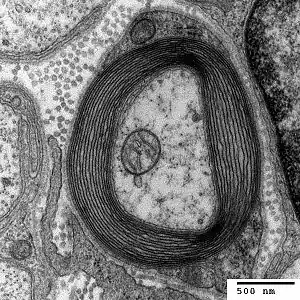

Vertebrates

Myelin is considered a defining characteristic of the jawed vertebrates (gnathostomes), though axons are ensheathed by a type of cell, called glial cells, in invertebrates.[15][16] These glial wraps are quite different from vertebrate compact myelin, formed, as indicated above, by concentric wrapping of the myelinating cell process multiple times around the axon. Myelin was first described in 1854 by Rudolf Virchow,[17] although it was over a century later, following the development of electron microscopy, that its glial cell origin and its ultrastructure became apparent.[18]